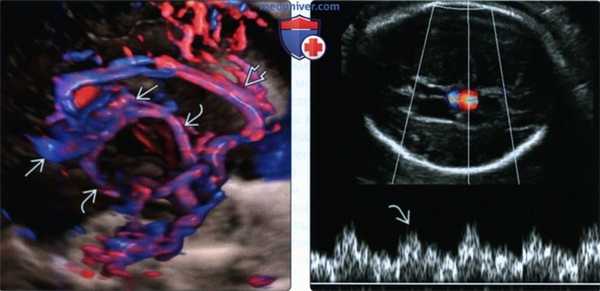

(Слева) В III триместре беременности при УЗИ в сагиттальной плоскости по средней линии видно случайно обнаруженное гипоэхогенное новообразование, удлиненная часть которого идет кзади в направлении верхнего сагиттального синуса.

(Справа) При ЦДК в этой же плоскости подтверждается наличие АВГ с турбулентным кровотоком - типичным признаком анастомоза. Чаще всего АВГ обнаруживается в III триместре беременности. Необходимо дальнейшее обследование для выявления признаков сердечной недостаточности с высоким сердечным выбросом.

(Слева) При ЦДК и 3D УЗИ у этого же пациента видны расширенная около-мозолистая артерия и АВГ, а также множественные глубокие артерии сосудистой оболочки, впадающие в анастомоз. До 80% сердечного выброса плода может перенаправляться в его головной мозг.

(Справа) При импульсно-волновом допплеровском УЗИ видно превращение волны венозного кровотока в волну артериального, что является характерным признаком наличия анастомоза. Высокая скорость кровотока в конце концов ведет к декомпенсации со стороны сердца.